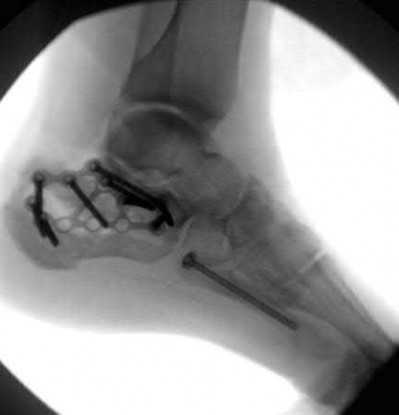

A 64-year-old woman is thrown off a horse, sustaining the injury shown in Figures A and B. She undergoes surgical fixation as seen in Figures C through E. What is the most commonly reported complication of this procedure?

The patient in the scenario has a 2-part proximal humerus fracture treated with a locking plate as seen in Figures A-E. The most common complication with the use of this implant is screw penetration. The terms screw cut out and penetration are often used interchangeably in the literature with cut out appearing more frequently in reports regarding intertrochanteric fractures.

Owsley et al retrospectively reviewed 53 proximal humerus fractures treated with locking plates and the same post-operative protocol. The most common complication was screw cut out or penetration, followed by varus displacement. They concluded that 3 and 4-part fractures in patients over 60 years have a higher incidence of failure.

Agudelo et al retrospectively reviewed 153 patients at a level-one trauma center treated with proximal humerus locking plates, investigating modes of failure for the implant. They determined that varus malreduction (head-shaft angle